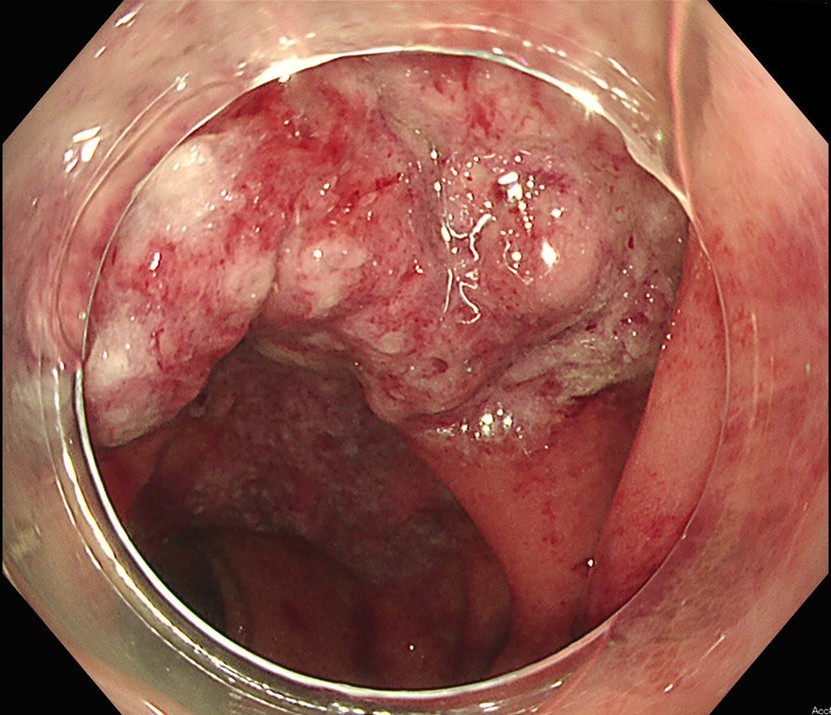

内視鏡検査(大腸カメラ)

大腸カメラが最も重要な診断方法です。

- 腸の粘膜を直接観察し、虚血によるむくみ、赤み、出血、そして特徴的な潰瘍(ただれ)を確認します。

- 典型的な例では、横行結腸からS状結腸にかけて、縦に走るような潰瘍が見られます。

- 潰瘍性大腸炎やクローン病といった炎症性腸疾患など、他の病気と区別するためにも役立ちます。

- ただし、お腹に強い炎症が起きている場合や、腸が壊死している可能性が高い場合は、検査ができないことがあります。